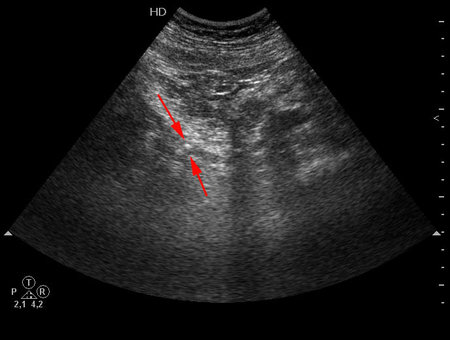

Пожилой мужчина с невыраженными болями в пояснице слева и микрогематурией.

УЗИ инспекция мочеточника. Sonographic inspection of an ureter

ого! до юкставезикального отдела инпекция